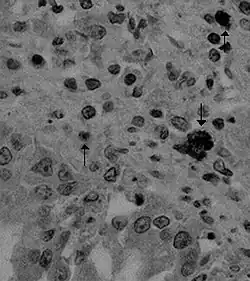

Canine coronavirus antigen (arrows) in canine lung tissue